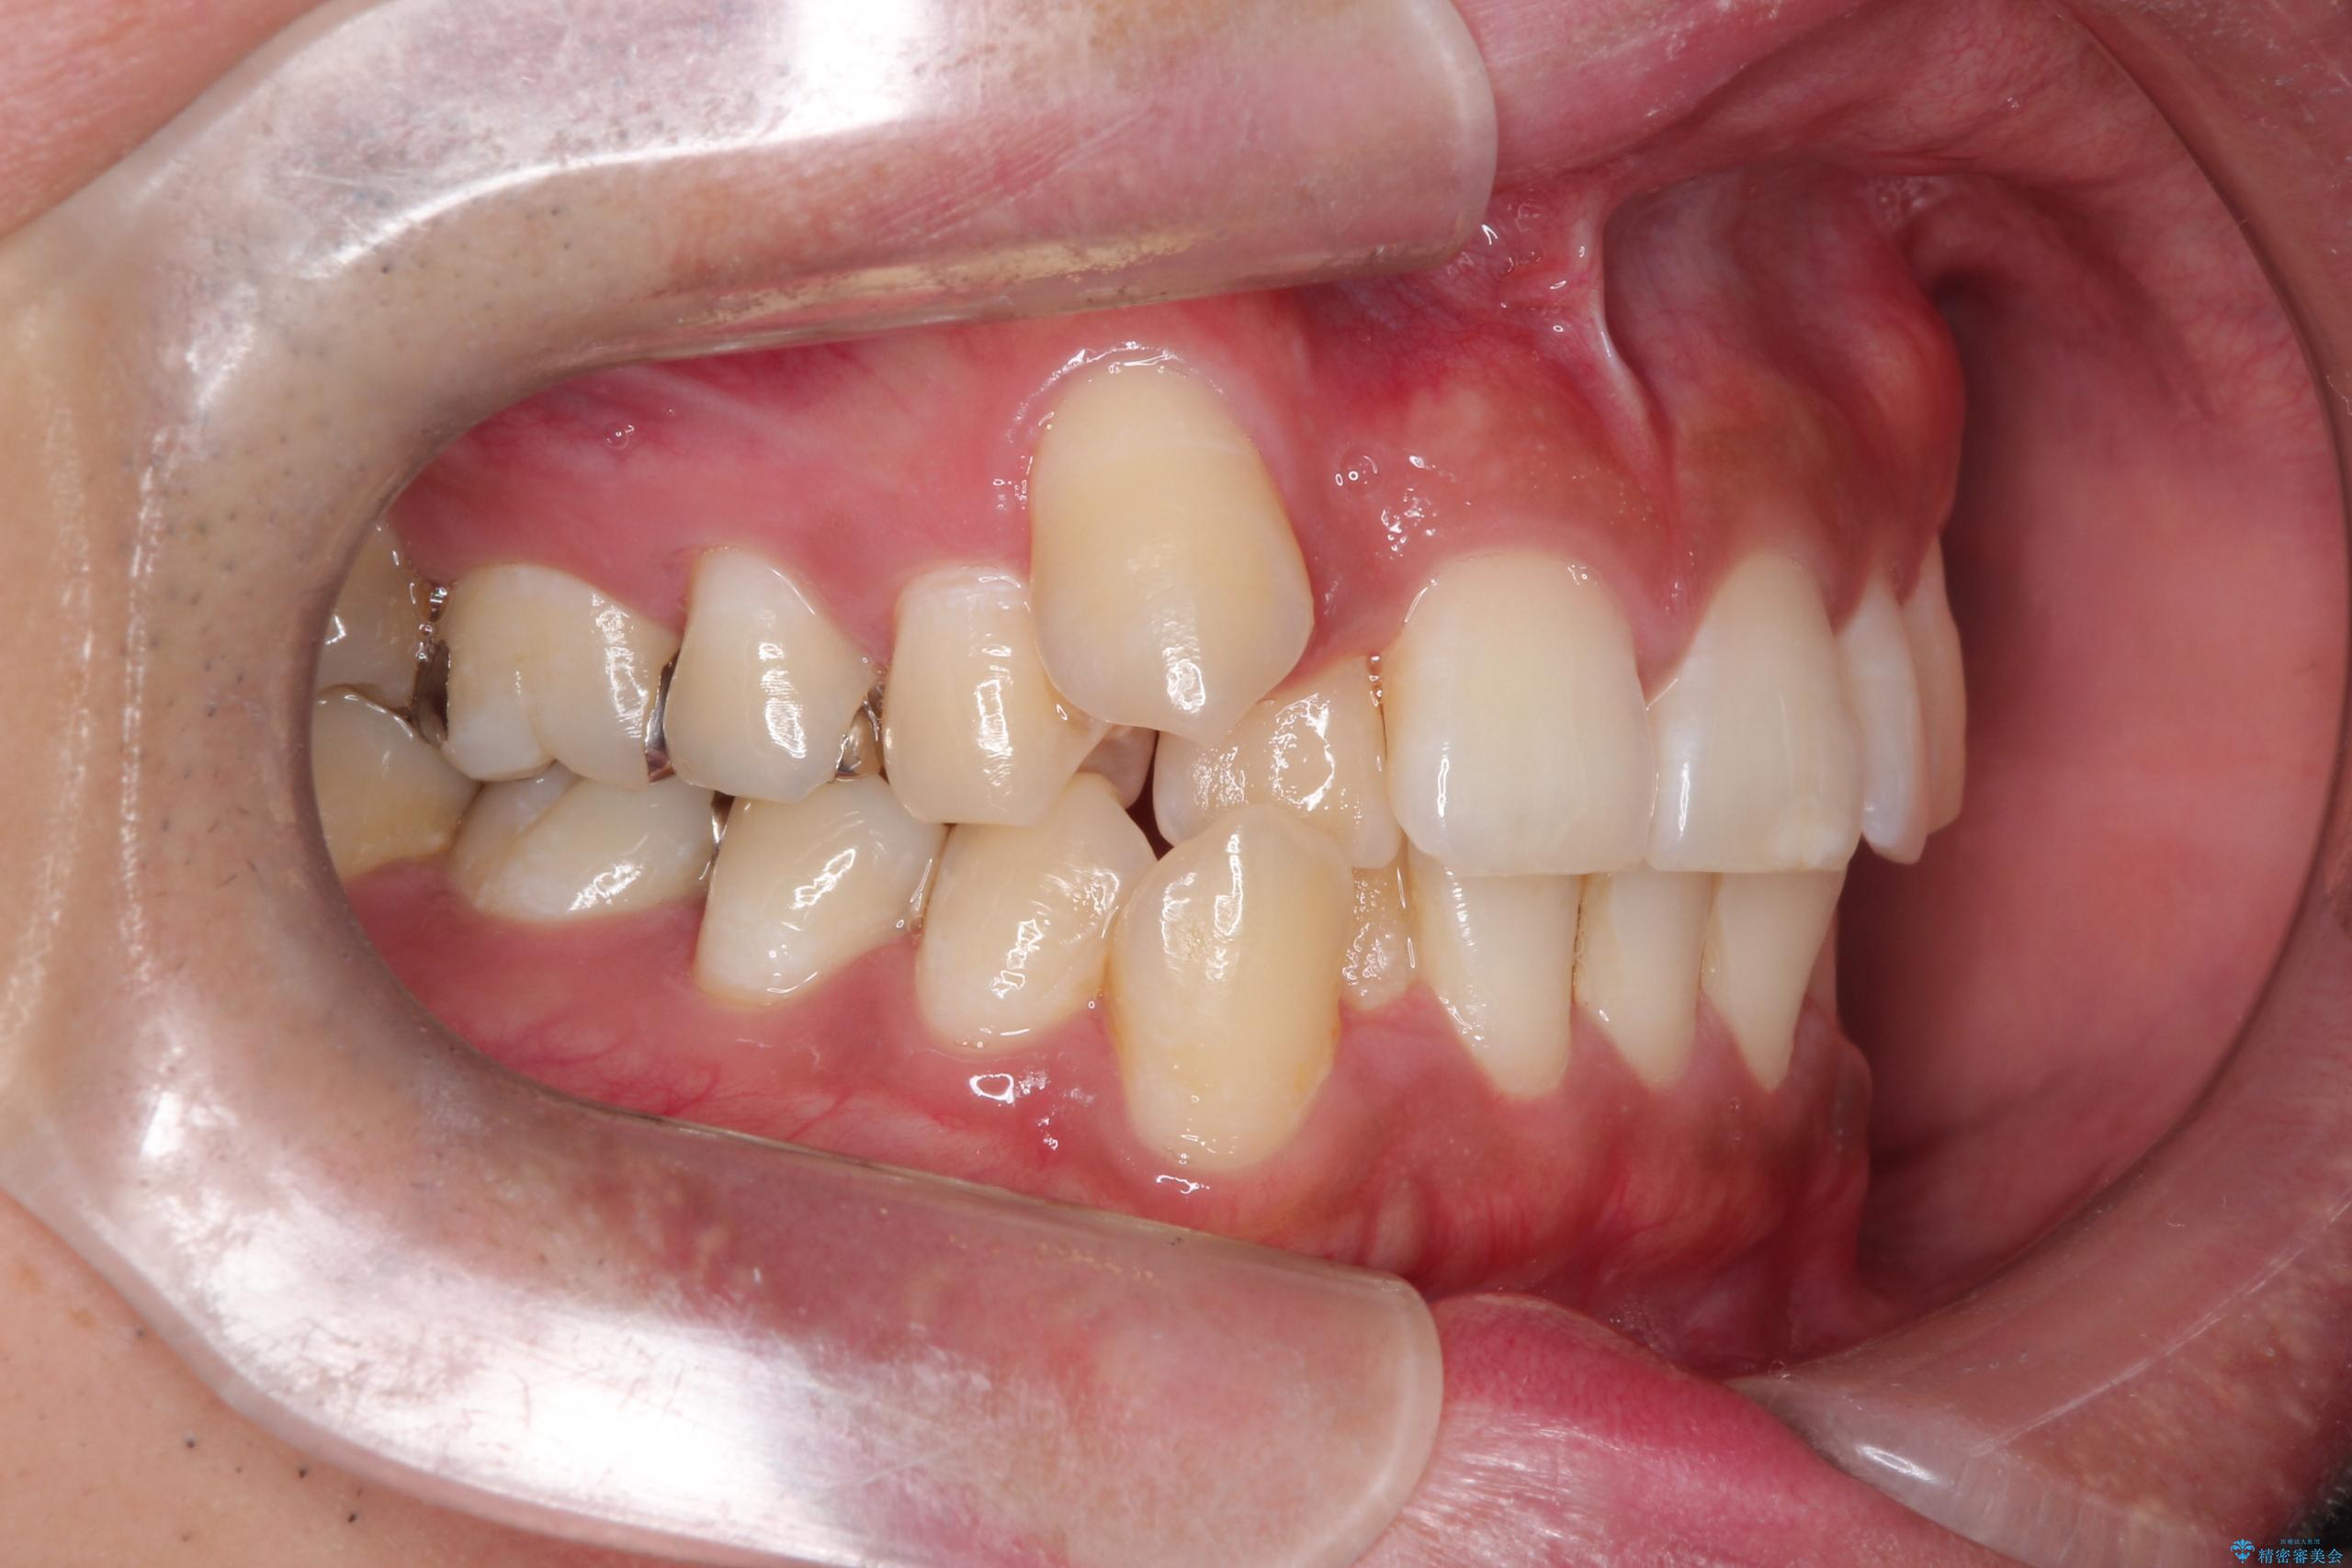

【ワイヤー矯正】八重歯と下の歯の凸凹を治したい

- 主訴:右上の八重歯と、下の歯の凸凹を治したい

上顎右側第一小臼歯と下顎右側第一小臼歯を抜歯しワイヤー矯正を行いました。

右側2級、左側1関係だったため、右側上下第一小臼歯を抜歯し、ワイヤー矯正を行いました。